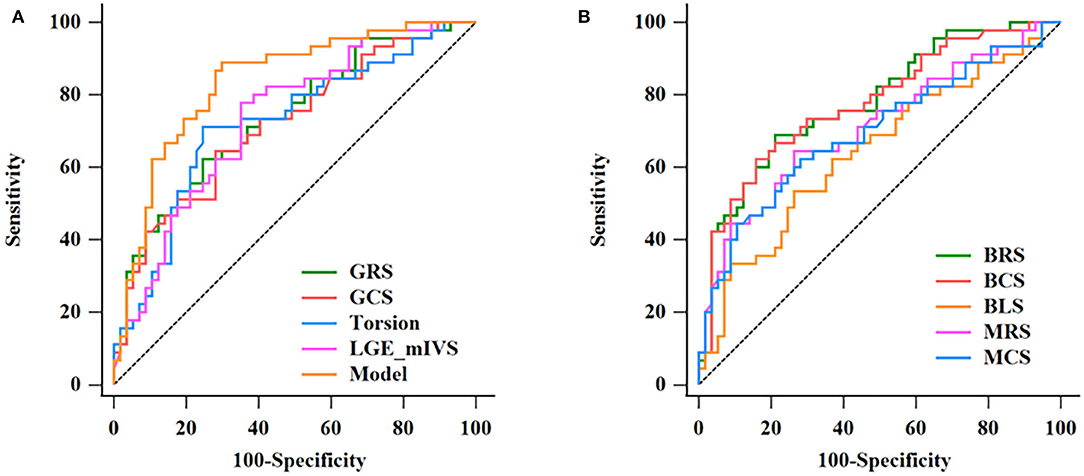

Results: Global radial strain (GRS), global circumferential strain (GCS), and LV torsion were significantly higher in the HCM group than in the HHD group (GRS, 21.18 ± 7.52 vs. 14.56 ± 7.46%; GCS, −13.34 ± 3.52 vs. −10.11 ± 4.13%; torsion, 1.79 ± 0.69 vs. 1.23 ± 0.65 deg/cm, all P < 0.001). A similar trend was also seen in the corresponding strain rate. As for segmental strain analysis, basal radial strain (BRS), basal circumferential strain (BCS), basal longitudinal strain (BLS), mid-radial strain (MRS), and mid-circumferential strain (MCS) were higher in the HCM group than in the HHD group (all P < 0.001). The receiver operating characteristic (ROC) results showed that the area under the curve (AUC) of LGE in the mid-interventricular septum (mIVS) was the highest among global and segmental LGE analyses. On the multivariate regression analysis, a combined model of LGE (mIVS) with GRS obtained the highest AUC value, which was 0.835 with 88.89% sensitivity and 70.18% specificity, respectively. In addition, for patients with HCM, GRS, GCS, and global longitudinal strain had correlations with LV ejection fraction (LVEF), maximum interventricular septum thickness (IVST max), and left ventricular mass index (LVMi). Torsion was mildly associated with LVEF.

The results of the ROC analysis to discriminate between HCM and HHD are shown in Table 4. GRS (AUC: 0.734, sensitivity: 62.22%, specificity: 75.44%, P < 0.001), GCS (AUC: 0.718, sensitivity: 64.44%, specificity: 71.93%, P < 0.001), and corresponding strain rate could distinguish HCM from HHD. For segmental strain parameters, the AUCs of BRS, BCS, BLS, MRS, and MCS for discriminating between HCM and HHD were 0.781, 0.776, 0.644, 0.711, and 0.697, respectively (all P < 0.001). The torsion cutoff value of > 1.40 differentiated HCM from HHD with a sensitivity of 71.11% and a specificity of 75.44%. The AUC of LGE (mIVS) was 0.735, which was the highest in the global and other segmental LGE analyses (all P < 0.05). Overall, BRS showed the highest diagnostic performance and the value of the AUC was 0.781 (all P < 0.05). On the multivariate regression analysis, the combination model of LGE (mIVS) with GRS obtained the highest AUC value, which was 0.835 with 88.89% sensitivity and 70.18% specificity, respectively (Table 5). DeLong's test showed that the AUC of a combined model of GRS with LGE (mIVS) was higher than those of GRS, GCS, torsion, and LGE (mIVS) (all P < 0.05) (Figure 4).

Figure 4. Discrimination of HCM and HHD by CMR parameters. The ROC curves in discrimination between HCM and HHD for single CMR parameters and the multivariate regression model are given in Table 5 (A). The AUC of combination model was the highest (0.835). The ROC curves of BRS, BCS, BLS, MRS, MCS in discrimination between HCM and HHD group (B). HCM, hypertrophic cardiomyopathy; HHD, hypertensive heart disease; ROC, receiver operating characteristic; CMR, cardiovascular magnetic resonance; AUC, area under the curve; GRS, global radial strain; GCS, global circumferential strain; LGE, late gadolinium enhancement; mIVS, mid interventricular septum; BRS, basal radial strain; BCS, basal circumferential strain; BLS, basal longitudinal strain; MRS, mid radial strain; MCS, mid circumferential strain.